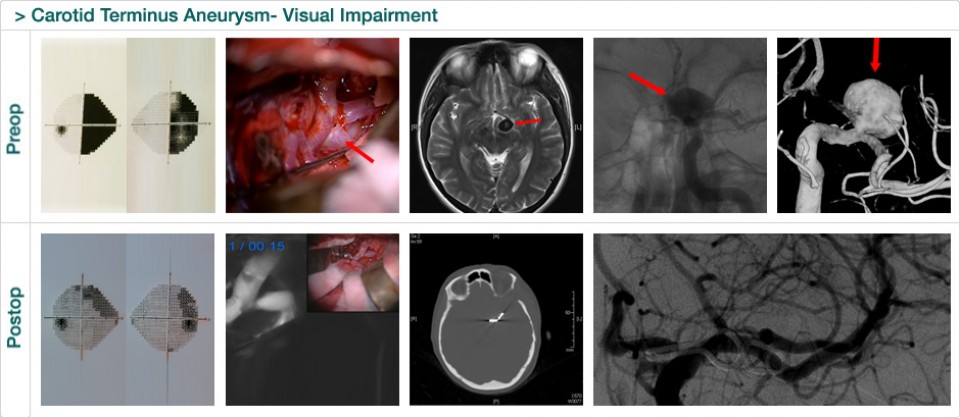

Dr. Attia is an attending neurosurgeon and the director of skull base surgery service in the department of neurosurgery at Sheba Medical Center in Tel HaShomer. His specialty focuses on skull base and cerebrovascular neurosurgery.